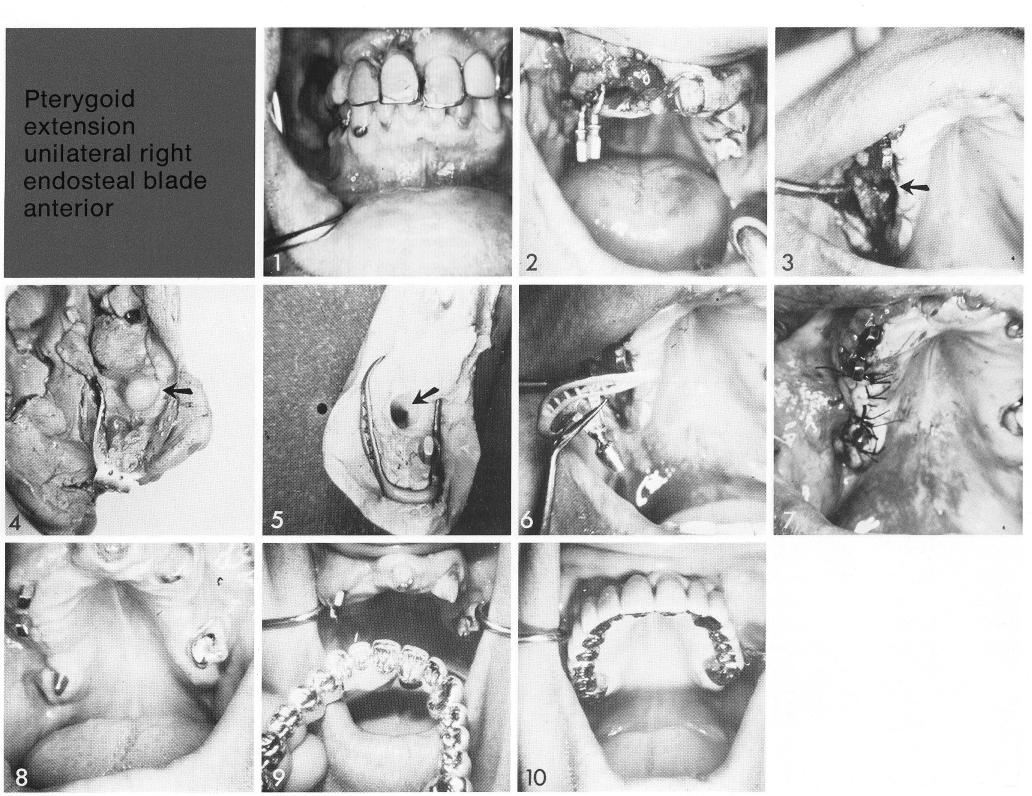

Pterygoid extension

unilateral right endosteal blade

anterior

Anteriorly the site is limited by a wide open socket. A short span of bone exists between the open socket and an invaginated sinus (3, arrow). An open-socket bladevent is used to counterbalance the teeth, and a unilateral subperiosteal implant posteriorly (4-6) to avoid the fragile area. Thus a combination of implant types counterbalances natural teeth (8) to support a fixed prosthesis (10).

1 Short span of maxillary bone exists between the open socket and sinus